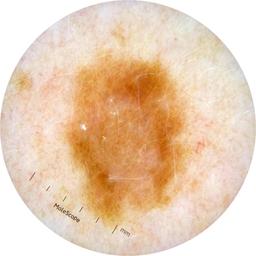

ISIC_1376863

IP_6274125

IL_8319447

Clinical

Field Value

acquisition_day 229

age_approx 40

anatom_site_general oral/genital

anatom_site_special oral or genital

concomitant_biopsy False

diagnosis_1 Benign

diagnosis_confirm_type single image expert consensus

family_hx_mm True

image_manipulation instrument only

image_type dermoscopic

lesion_id IL_8319447

patient_id IP_6274125

personal_hx_mm True

sex female